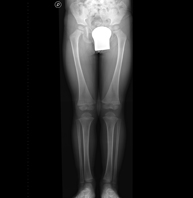

- Telemetría EEII (Extremidades Inferiores)

Técnica mediante la cual, utilizando rayos X, se obtienen imágenes de la totalidad de ambas extremidades inferiores para su estudio, valorando especialmente la presencia de dismetrías entre ambas.